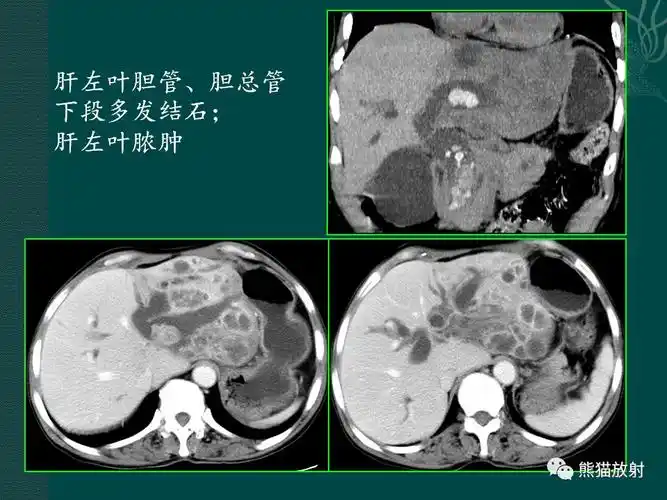

胆系病变丨ct及mri诊断